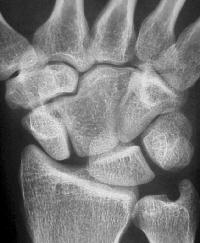

Clinical Example: Congenital capitate malformation with capitate trapezoid articulation and scapholunate diastasis

This patient was evaluated for wrist pain following a wrist sprain.

Plain films demonstrate an unusual capitate contour, articulating with the proximal trapezoid. There is a wide scapholunate interval.